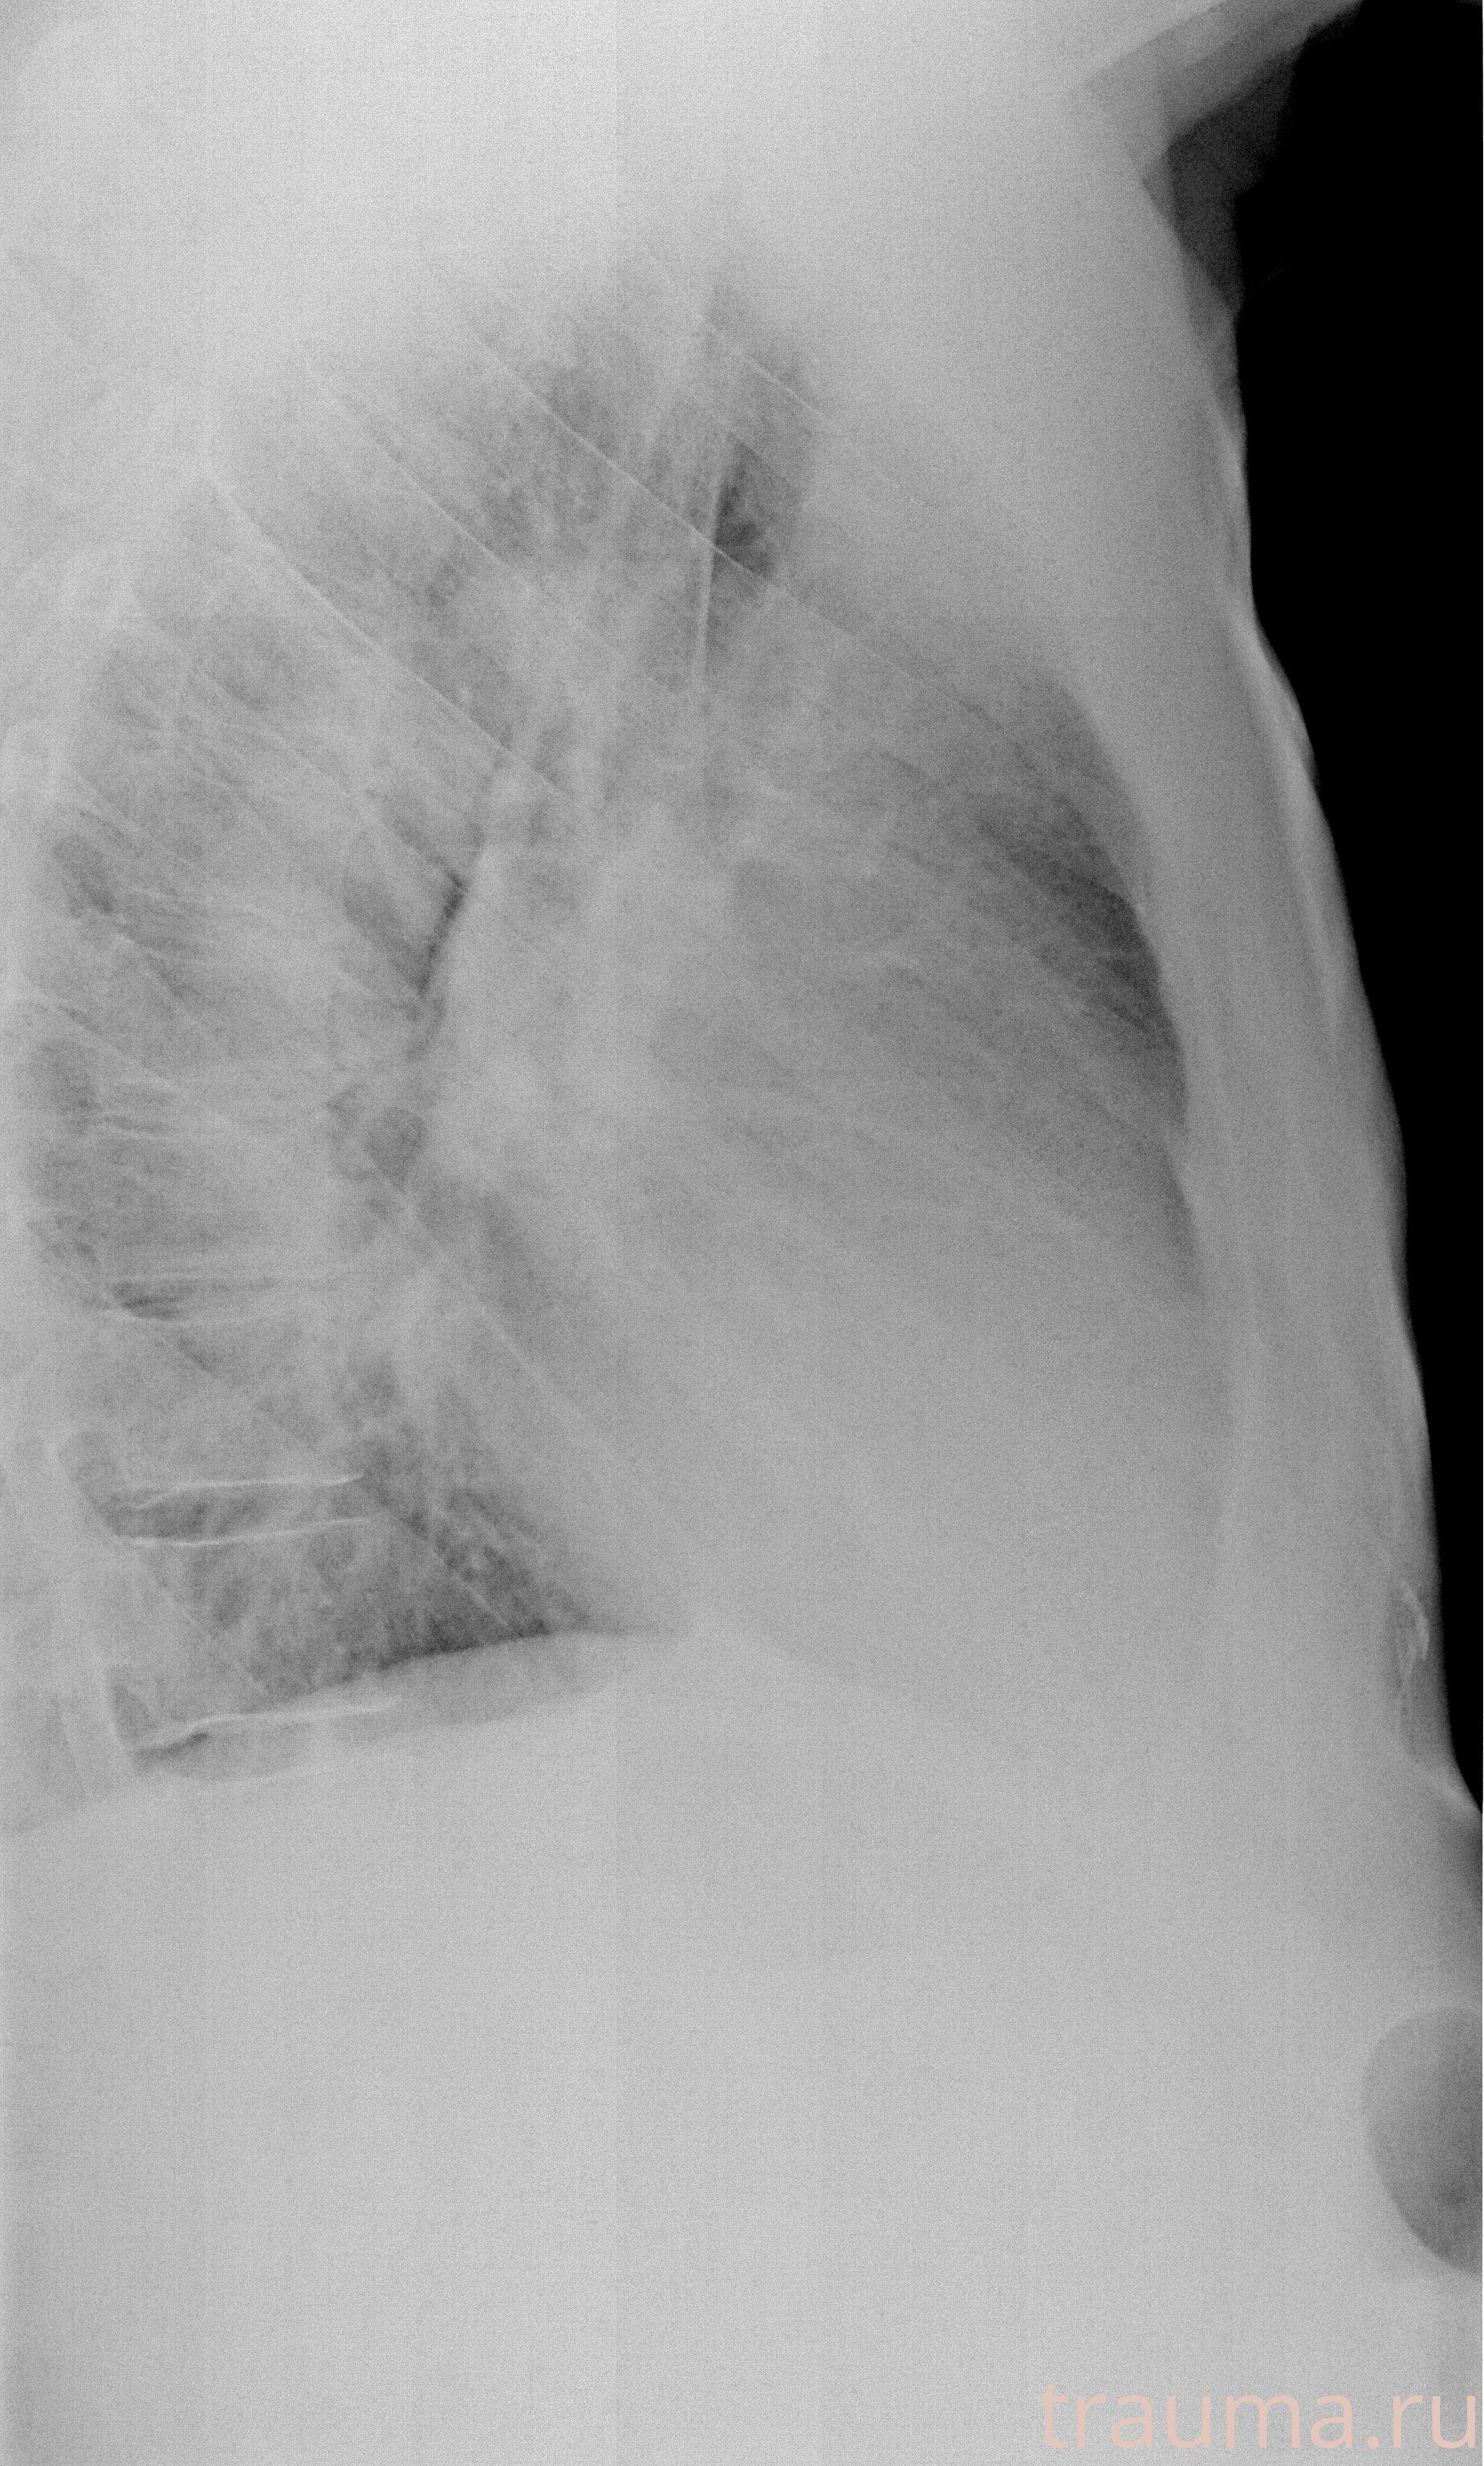

Рентген на дому: по вашему адресу приезжает врач-рентгенолог, травматолог-ортопед с мобильным рентгеновским аппаратом, проводит диагностику травмы или заболевания, делает необходимые рентгенограммы, дает рекомендации по дальнейшему лечению. Получить качественные снимки в домашних условиях возможно благодаря уникальной методике, разработанной МосРентген Центром для института  Склифосовского